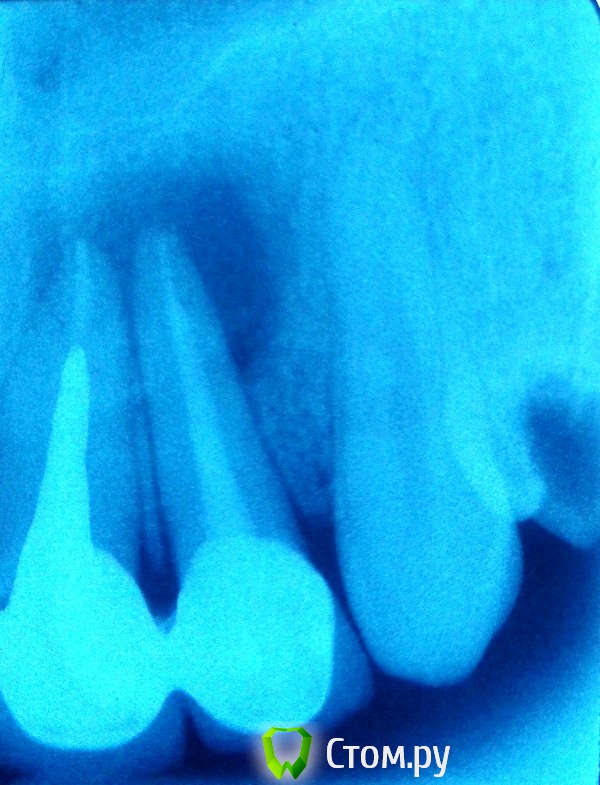

bilal Опубликовано 16 февраля, 2014 Поделиться Опубликовано 16 февраля, 2014 Выкладываю результаты моей первой операции по резекции верхушек 2.1, 2.2 через 3 месяца. Начало здесь http://forum.stom.ru/topic/22547-pomogite-sovetom-oslozhenie-posle-lechenie/ . Снимок не очень четкий, но результат очевиден. 1 1 Ссылка на комментарий

bilal Опубликовано 16 февраля, 2014 Автор Поделиться Опубликовано 16 февраля, 2014 (изменено) По данному контрольному снимку, кроме как о некомпетентности его выполнившего судить нельзя!!! Никаких результатов не видно, да и к тому же 3 мес слишком малый срок для репарации кости, видной на рентгене. Для контроля, ваши снимки должны быть ТОЛЬКО с позиционерами!Оба снимка сделаны с позиционерами. 3 мес достаточно, чтобы судить о положительном продвижении. И на снимке явно видно значительное уменьшение диструкции. Изменено 16 февраля, 2014 пользователем bilal Ссылка на комментарий

ПалСаныч Опубликовано 30 марта, 2014 Поделиться Опубликовано 30 марта, 2014 А мне кажется bilal молодец. Прежнего объема кисты нет? - нет. Сколько простоят, столько простоят. А судя по динамике еще постоят. Будет рецидив, так удалит. А пока со своими зубками ходит человек. Так что мучился не зря))) 1 Ссылка на комментарий

ПалСаныч Опубликовано 31 марта, 2014 Поделиться Опубликовано 31 марта, 2014 Олег Юрьевич, буду только рад восполнить пробел с своих знаниях, если не прав. Но если бы в канале была инфекция, разве уменьшился бы объем костной полости? Нет. Образовалась бы грануляционная ткань, где бы росла флора, появился свищ и тогда мы признаем, что все сделано зря.В данном случае, костная полость уменьшается, причем весьма неплохо, особенно вокруг корня 2.2 Где я ошибаюсь? Ну и вопрос в студию от меня - какой идеальный материал для пломбирования корня перед резекцией и какой материал для ретроградной пломбировки? У кого какие предпочтения? если данный вопрос освещался, дайте ссылку пожалуйста))) Ссылка на комментарий